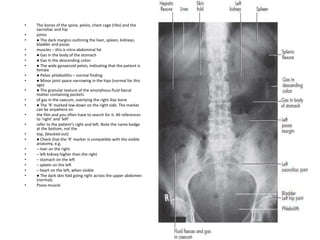

Normal AXR

11th rib

Hepatic flexure

Gas in

stomach

T12

Gas in caecum

Iliac crest

Femoral head

SI joint

Gas in sigmoid

Transverse colon

Splenic flexure

Psoas margin

Sacrum

Left kidney

Liver

Bladder

• The bones of the spine, pelvis, chest cage (ribs) and the

sacroiliac and hip

• joints

• ● The dark margins outlining the liver, spleen, kidneys,

bladder and psoas

• muscles – this is intra-abdominal fat

• ● Gas in the body of the stomach

• ● Gas in the descending colon

• ● The wide gynaecoid pelvis, indicating that the patient is

female

• ● Pelvic phleboliths – normal finding

• ● Minor joint space narrowing in the hips (normal for this

age)

• ● The granular texture of the amorphous fluid faecal

matter containing pockets

• of gas in the caecum, overlying the right iliac bone

• ● The ‘R’ marked low down on the right side. The marker

can be anywhere on

• the film and you often have to search for it. All references

to ‘right’ and ‘left’

• refer to the patient’s right and left. Note the name badge

at the bottom, not the

• top, (blacked out)

• ● Check that the ‘R’ marker is compatible with the visible

anatomy, e.g.

• – liver on the right

• – left kidney higher than the right

• – stomach on the left

• – spleen on the left

• – heart on the left, when visible

• ● The dark skin fold going right across the upper abdomen

(normal).

• Psoas muscle